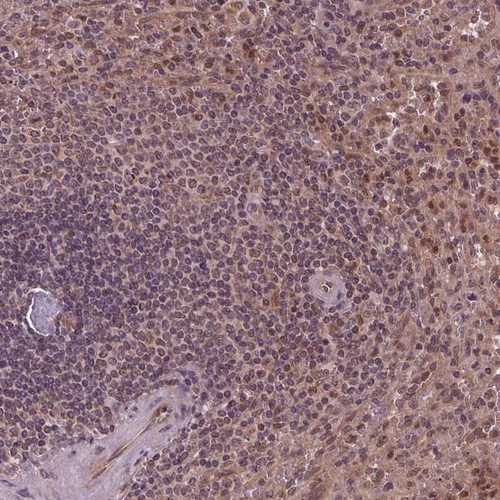

Immunohistochemical staining of human spleen shows moderate cytoplasmic positivity in cells in red pulp.